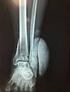

1 Complejo Cientifico Ortopedico Internacional "Frank País" Ciudad de La Habana, Cuba Tratamiento de las fracturas de pelvis Dr. Juan Alberto González Ruiz, 1 Dr. Yoel Reyes Alvarez, 2 Dr.C Rodrigo Alvarez Cambras, 3 Dr. Miguel Angel Rodríguez Angulo, 4 Dr. Ricardo Tarragona Reynoso 5 y Dr. Noel González Fundora 6 Resumen En el presente trabajo se aborda el tratamiento de las fracturas-luxaciones de pelvis y se analizan sus tendencias más actuales, se revisan las complicaciones y los resultados funcionales de las principales opciones de tratamiento, fundamentalmente la osteosintesis interna y la fijación externa. Se muestra también un listado de referencais bibliográficas que puede facilitar la búsqueda o ampliación de los conocimientos de los profesionales interesados en este tema. Palabras clave: pelvis, fracturas-luxaciones, fijador externo. El tratamiento adecuado de las fracturas-luxaciones de pelvis para cada paciente no solo se relaciona con el grado de lesión y dislocación ligamentosa u ósea, sino también con la presencia de lesiones en las extremidades, cabeza, tórax o abdomen.1 El especialista ortopédico habrá de estar presente en la reanimación inicial del paciente y estar incluido en el proceso de toma de decisiones. La primera prioridad es salvar la vida del paciente y esto depende de la completa comprensión de las posibles lesiones, la posibilidad de que continúe la perdida de sangre y de las lesiones pélvicas y sistémicas asociadas ( fig. 1). Los principios fundamentales del tratamiento son: Tratamiento temprano y agresivo con una apropiada resucitación. Inmediato desbridamiento quirúrgico de las heridas abiertas. Estabilización de las fracturas de pelvis. Toracotomía, laparotomía y hasta colostomía de urgencia, de ser necesario.